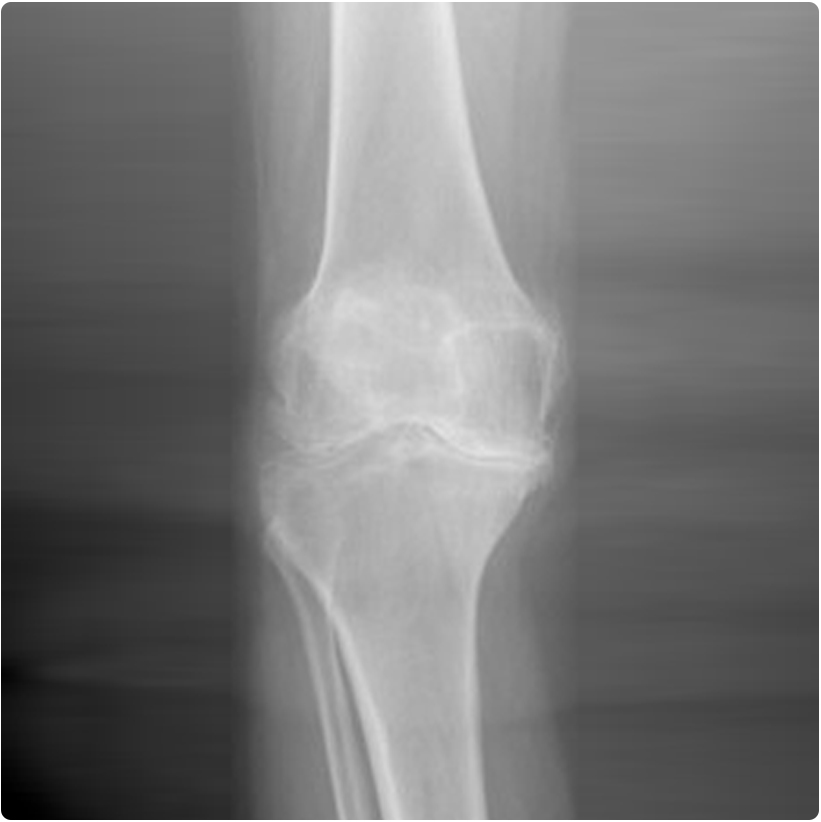

Halk arasında kireçlenme olarak bilinen hastalık eklemlerde oluşan ve kıkırdak kaybıyla seyreden bir durumdur. Aslında eklemde kireç-kalsiyum birikimi yoktur, röntgende aşınan kıkırdağın altındaki kemik dokusunun sertleşmesine bağlı olarak normalden daha beyaz görülmesi nedeniyle bu isim verilmiştir.

Eklem kıkırdağının aşınması ve kaybı yükün kemik tarafından daha fazla taşınmasına neden olur. Osteoartritte kıkırdak kaybı ile birlikte eklem sıvısı üreten zar (sinovyal doku) da hastalığa katılır. Kıkırdak yüzeyin kayganlaşmasını sağlayan sıvılar daha az üretilmeye başlanır. İlerledikçe vücudun hastalığı düzeltme çabasıyla eklem çevresi bağ ve kaslarda değişiklikler başlar, eklemin özellikle kenar bölgelerinde yükü paylaştırma çabasıyla kemik çıkıntıları (osteofitler) oluşur. Tüm bu bozukluklar ve düzeltme çabası hastada şikayetlere neden olur. Bu hastalık ileri yaşlarda ortaya çıkmaya başlar ve ilerlediğinde ağrı, hareket kısıtlılığı, eklemde şekil bozukluğuna sebep olur. Özellikle diz, kalça, ayak bileği, omuz, bel omurları gibi büyük eklemlerde görülse de parmak eklemleri gibi küçük eklemlerde de sıkça görülebilmektedir.

En önemli bulgu ağrıdır. Eklem ağrısıyla birlikte genellikle sertlik, hareket azalması veya hareket sırasında artan ağrı söz konusudur. Hastalık ilerledikçe eklem hareketlerinde kayıp belirginleşir, ağrı artar ve eklemde şekil bozukluğu ortaya çıkar ve örneğin diz eklemi eğilmeye başlar. Hastalığın olduğu vücut bölümünü kullanmak zor hale gelir, örneğin kalça veya dizde ilerlemiş osteoartrit varlığında yürüme işlevi giderek zorlaşır.